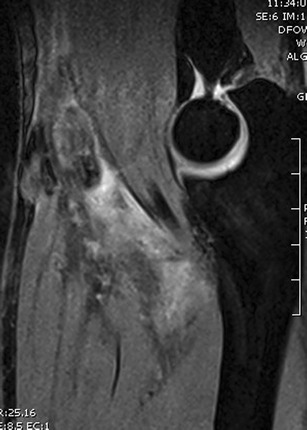

Magnetic resonance imaging [22, 23] (Fig. 4), in particular, the flexion-abduction-supination (FABS) view [24•], can be used for optimal visualization. For the FABS view, the patient is placed prone in the MRI scanner with the affected arm in full abduction above the patient’s head, with the elbow flexed to 90° and the forearm supinated [24•] (Fig. 5). Although an MRI may not be needed to confirm the diagnosis of a complete rupture, the FABS MRI view is especially helpful for the diagnosis and evaluation of partial ruptures and chronic ruptures. It allows for visualization of the entire course of the distal biceps tendon, evaluation for possible partial tear, the formation of scar tissue, and the amount of proximal retraction. This information will help the surgeon prepare for surgery.

Fig. 4.

Magnetic resonance image showing a complete distal biceps tendon avulsion. Reprinted with Permission from MoRe Foundation

Fig. 5.

A FABS view MRI is particularly helpful in partial or chronic tendon ruptures. It allows for a clear view of both the insertion and the course of the tendon. Reprinted with Permission from MoRe Foundation